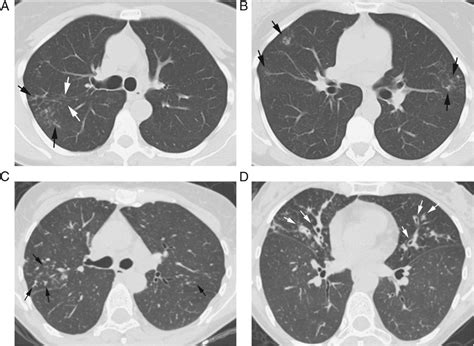

The tree in bud opacities appearance is fundamentally a reflection of airway pathology. On a CT scan, the "tree" component represents dilated, fluid-filled bronchioles (the smallest airways in the lung), while the "buds" represent the accumulation of mucus, pus, or fluid in the acini, which are the functional units of the lung located at the ends of these bronchioles. This pattern typically suggests that something is causing inflammation, infection, or obstruction within the small airways.

Because these opacities are located in the periphery of the lungs, they are easily distinguished from larger airway diseases. Radiologists look for these clusters of small nodules that connect to a branching structure. When you see this term on your report, it indicates that the air spaces are being filled with abnormal material, effectively "plugging" them and creating the characteristic visual pattern.